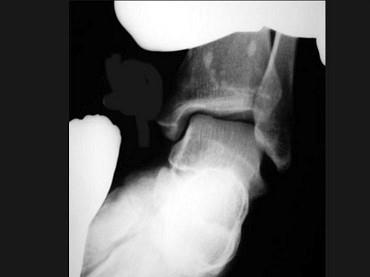

女,27岁,有外伤史,结合图像,最可能的诊断是?(?)A.骨斑点症B.骨梗死C.骨岛D.皮肤骨膜肥厚症E.石骨症

问题 女,27岁,有外伤史,结合图像,最可能的诊断是?(?)

选项 A.骨斑点症 B.骨梗死 C.骨岛 D.皮肤骨膜肥厚症 E.石骨症

答案 A